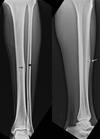

Tibia Stress Fx most common in? physical exam findings? imaging? Work up? When to operate? Highest likely hood of non-union

* athletes and military recruits, especially after a change in type, intensity, or duration of an activity. * limp or abnormal weight-bearing, with focal tenderness and a positive one-legged hop test * Xrays: Will be normal 2-3+ weeks. Cortical thickening will show up after several weeks. MRI: treatment of choice, high sensitivity and specificity. ○ Bone marrow edema: T2 weighted stress reaction, precursor to stress fx ○ Linear areas of low signal intensity: T1 weighted image, indicative of fx * Tx: activity modification, eval of vitD, osteoporosis/penia, female triad. Eval by endo. * IMN, for fx of anterior cortex, "dreaded black line" load sharing with an intramedullary tibial nail has been used to decrease the risk of delayed or nonunion of this tension-sided fracture. * fractures of anterior cortex of tibia have highest likelihood of delayed healing or non-union ## Footnote Tc-99m bone scan: increased uptake, less specific than MRI tibia is the most frequent stress fracture location in most series in both athletes and modern military training. The anterior midshaft region of the tibia may be at higher risk secondary to tensile forces and a relative paucity of blood supply.